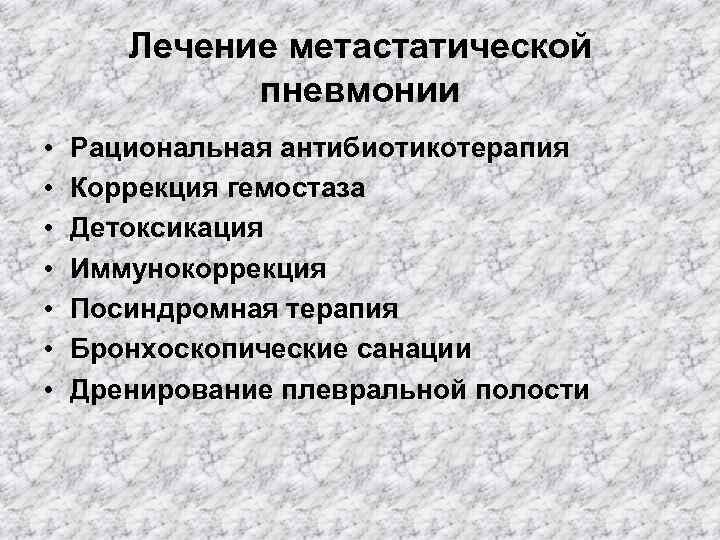

Лечение метастатической пневмонии • • Рациональная антибиотикотерапия Коррекция гемостаза Детоксикация Иммунокоррекция Посиндромная терапия Бронхоскопические санации Дренирование плевральной полости

Лечение метастатической пневмонии • • Рациональная антибиотикотерапия Коррекция гемостаза Детоксикация Иммунокоррекция Посиндромная терапия Бронхоскопические санации Дренирование плевральной полости